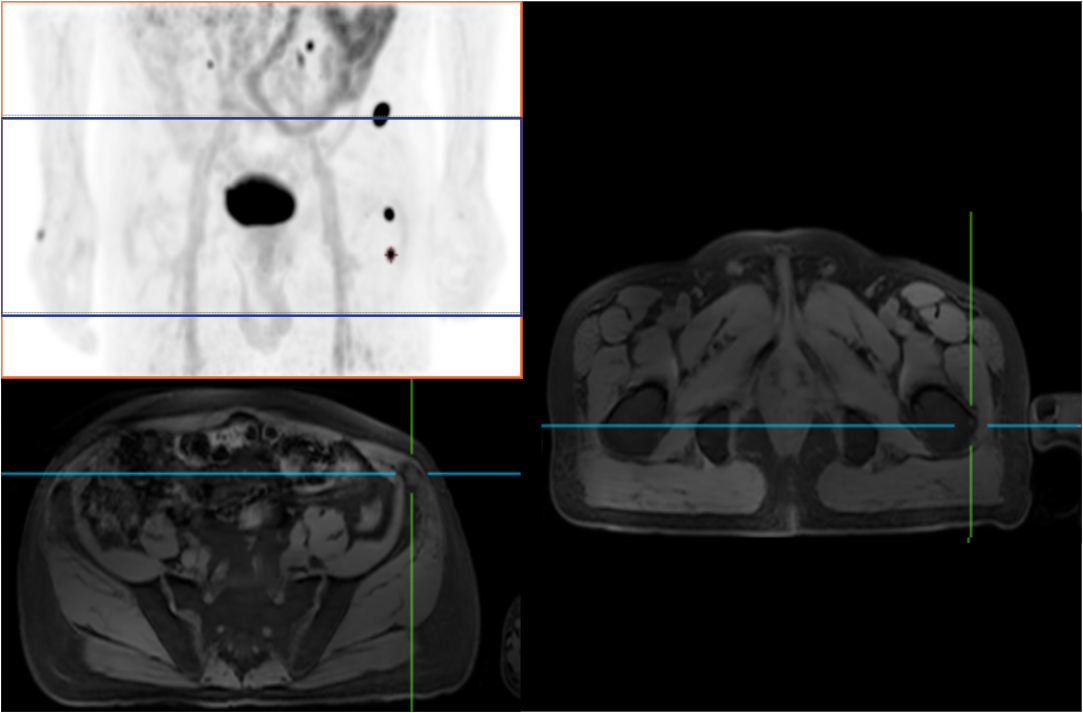

Compared with the conventional PET system with AFOV ranging between 20cm and 25cm, the 32cm long AFOV not only improves the sensitivity of the system, but also basically covers main organs of the whole body and the regional lymphatic system where metastasis may occur, and makes it possible to realize cancer TN staging in one bed position.

Traditionally, a PET/MR scan of a tumor patient takes about 35 to 50 minutes. The long AFOV can further optimize the PET/MR tumor scanning scheme. In other words, it can optimize the decision about whether to scan the whole body based on whether the tumor patient has regional lymphatic metastasis after regional PET/MR scan, potentially saving scan time for patients without metastasis.

In August 2019, Peking Cancer Hospital introduced United Imaging Healthcare's integrated PET/MR to make an in-depth exploration and optimization of cancer TNM staging under long AFOV. More than 500 examples of scanning various organs proved that long AFOV PET/MR could greatly increase the scan range over one bed position and improve the efficiency of cancer TNM staging.

The following are the cases of optimized TNM staging of breast cancer, esophageal cancer, prostate cancer and other diseases under the long axial field of "spatio-temporal integration" ULTRA-clear TOF PET/MR. Thanks to Capital Medical University Xuanwu Medical Treatment for providing the image.